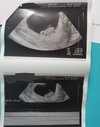

Załączniki

• IMG_20210907_075315.jpg

IMG_20210907_075315.jpg

906,1 KB · Wyświetleń: 103